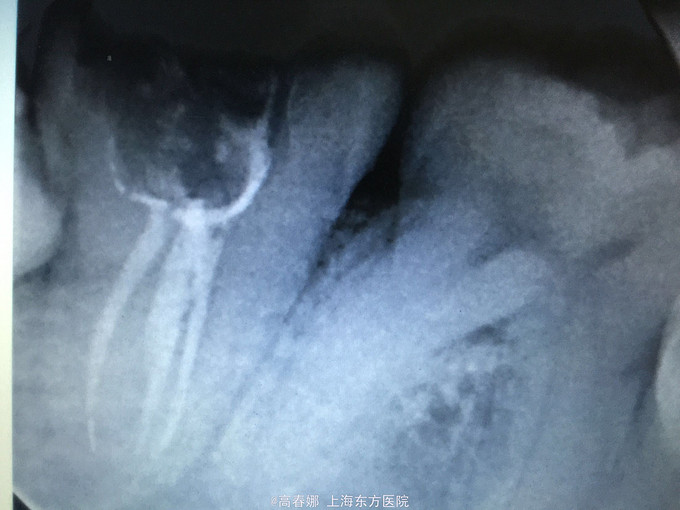

检查:47牙合面大面积龋坏,探及穿髓点,探痛(+++),叩诊(+-),松动无,牙龈无红肿,牙周袋约2-3mm,冷诊(+)。

诊断:47急性牙髓炎 治疗计划:47常规根管治疗后冠修复。

下颌第二磨牙C行根管发生率很高,根管形态不规则,给根管预备及充填带来一定的困难。随着镍钛器械的广泛使用,由于器械使用次数的限制,器械分离的发生概率也有所上升。此病例,器械分离发生在根尖1/3处,在没有症状的情况下,不予取出,作为根充的一部分,但应观察随诊。